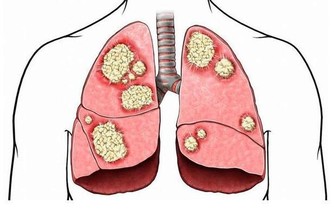

5、早戒菸,保護心腦

戒菸不僅僅可以保護心腦血管健康,還有助於預防癡呆症的發生。吸煙的人患上血管性癡呆的可能性比不吸煙的人要高出很多。所以,如果你不想自己以後患上老年癡呆症,就及時戒菸吧。